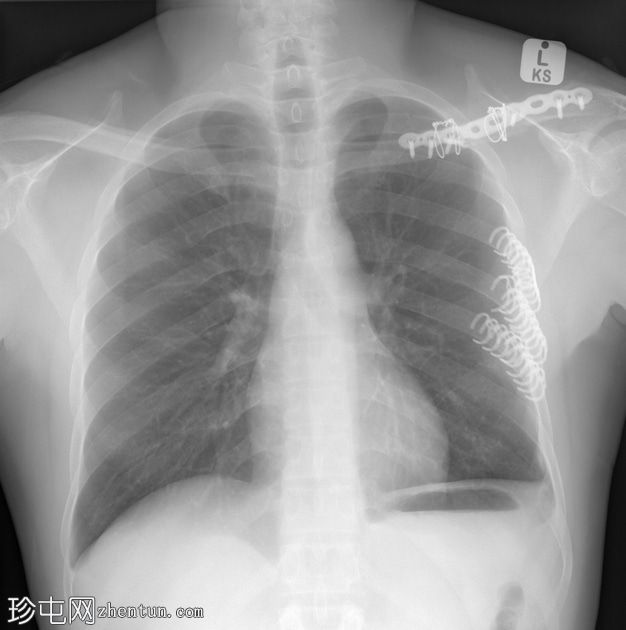

先前在外部医疗机构接受肋骨切开复位内固定 (ORIF) 后进行的 X 光检查。先前曾遭受高速摩托车事故造成的多发性创伤。

侧面

3D 肋骨夹正下方固定左侧第 5 至第 7 肋骨。骨性愈合良好,对位良好。

先前创伤和血胸导致左侧膈肌轮廓消失,肋膈角残留。

本病例为高速摩托车事故后,使用3D钛肋骨夹固定先前移位的左肋骨骨折的病例。